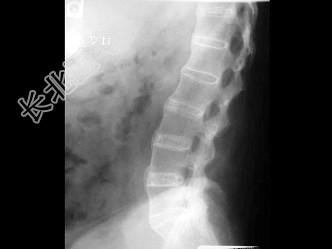

- 单项选择题男,21岁, 腰部不适,晨起加重半年余, X线检查如图,最可能的诊断是 ( )

A、类风湿关节炎

B、脊椎退行性变

C、强直性脊柱炎

D、化脓性脊柱炎

E、阻滞椎